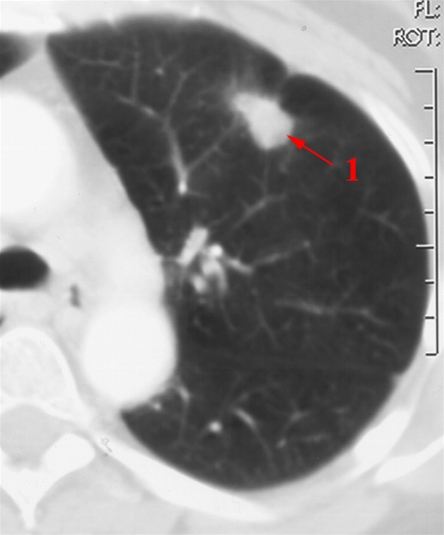

CT-billedet viser kantet, men velafgrænset fortætning fortil i venstre lunges overlap (pil). De radierende strøg ud i lungevævet er karakteristiske for en malign tumor.